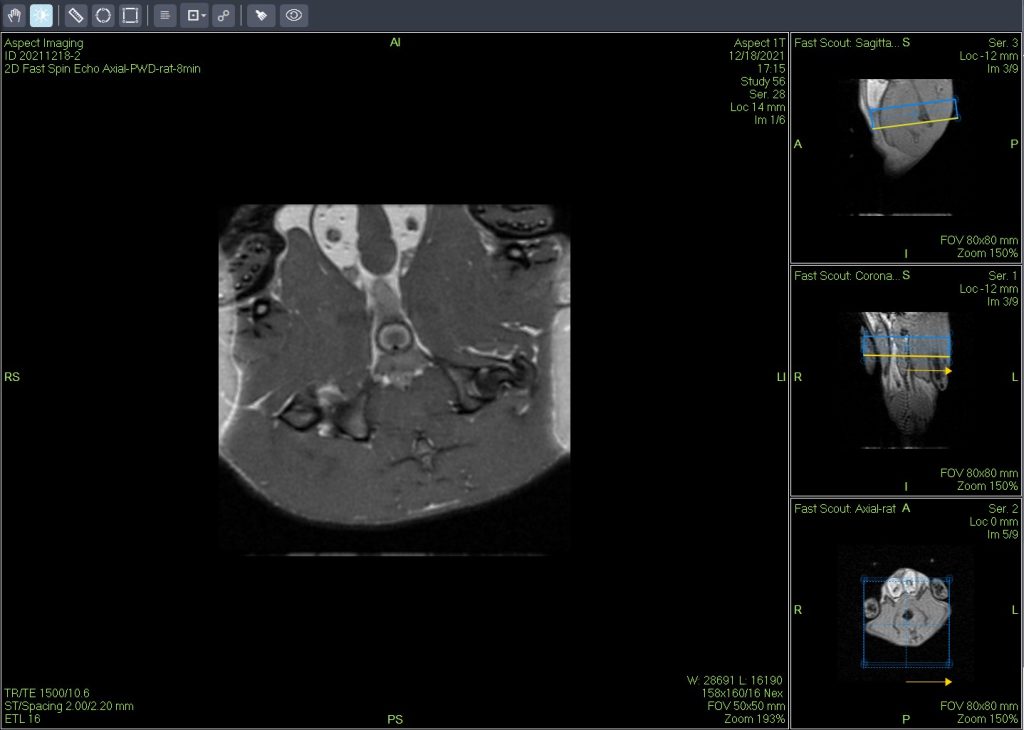

小鼠皮下肿瘤MRI造影成像效果与造影剂代谢过程研究。

使用仪器: 小动物核磁共振成像仪NM20-060H-I 其他相关应用: 核磁共振造影剂弛豫率分析造影剂分析案例 核磁共振成像与分析技术在生命科学领域应用解决方案

使用仪器: 小动物核磁共振成像仪NM21-040H-I 小动物核磁共振成像仪NM20-060H-I 小动物核磁共振成像仪NM42-040H-I